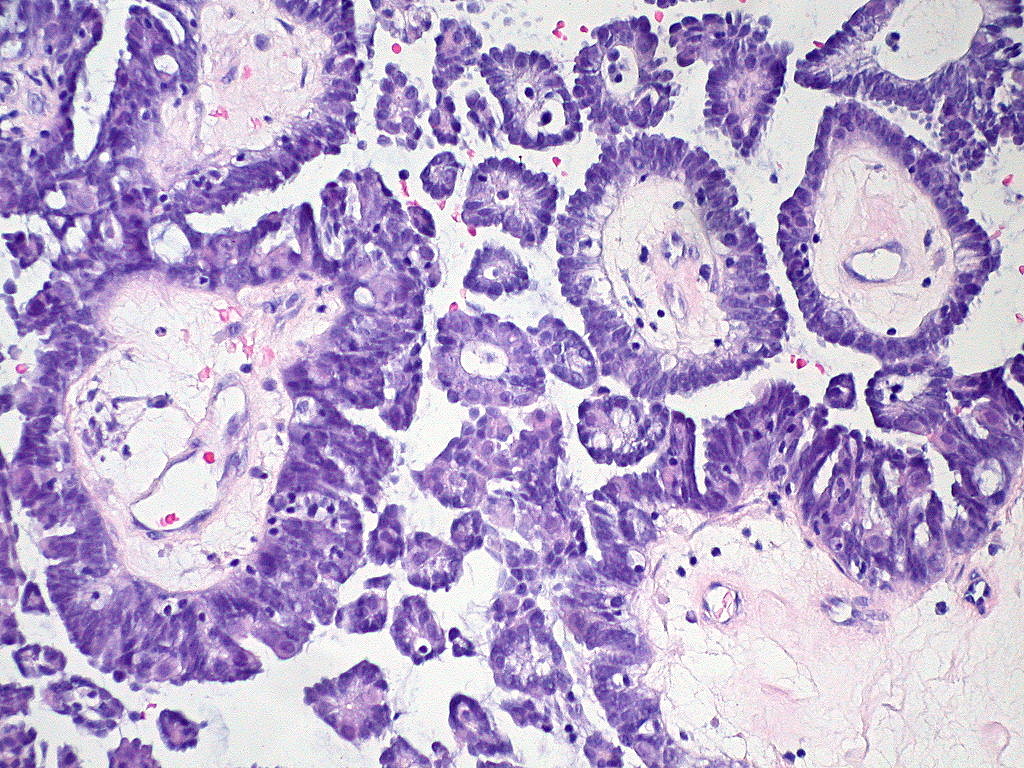

Ed Uthman / Flickr CC by 2.0